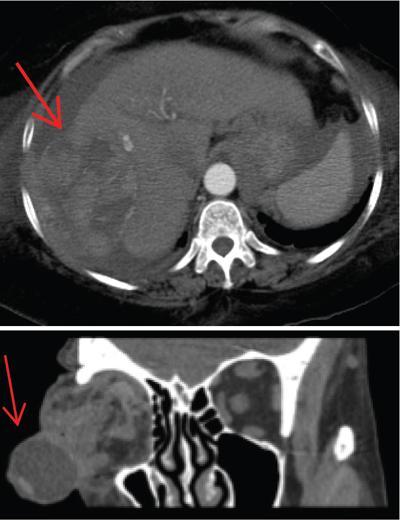

Shrinivas B. Desai, Ritu K. Kashikar, Shreya Shukla Radiological signs are classical and distinctive abnormalities characteristic of a disease. These can be seen on any imaging modality. Resemblance to commonly seen objects and patterns form the basis of radiological signs. The aim is to help the reader associate, understand and memorize these pathologies with the aid of signs. Various signs pertinent to hepatobiliary system are described in the chapter. Described on MRI when liver lesion shows a peripheral rim of high T2 signal intensity with the centre of the lesion appearing isointense to the background of noncirrhotic liver on T2WI mimicking an atoll. It is considered a characteristic sign of an inflammatory hepatic adenoma (image) but is only seen in about one-third of cases Extrinsic smooth impression over medial aspect of duodenum along its posteroinferior aspect, seen in pancreatic head pathologies like carcinoma. This sign is seen in pancreatic adenocarcinoma Presence of a persistently hyperattenuating dot within a lesion on arterial and portal venous CT. This corresponds with peripheral nodular enhancement seen on dynamic MR. Presence of bright dot suggests that the lesion is a hemangioma and helps in ruling out metastasis Ultrasound appearance of multiple cystic spaces or lesions that has been used to describe the appearance of an intraductal papillary mucinous neoplasm of the pancreas. Seen on contrast CT in portal hypertension. The appearance is based on resemblance to Medusa from Greek mythology. Dilated engorged paraumbilical veins radiating across umbilicus to join systemic veins is seen. This sign is seen in Caroli’s disease on contrast CT. Enhancing dots within dilated intrahepatic bile ducts represent portal radicles. Caroli’s disease Irregularly dilated pancreatic duct with multiple strictures and intervening dilatation with associated dilated side ductules resemble multiple lakes supplied by a single territory. Best seen in MRCP images. Chronic pancreatitis It is a finding on MRI and CT and is best seen on MRI T2-weighted and postcontrast T1-weighted sequences. Small necrotic/purulent areas in the pyogenic abscess ‘cluster’ together and then coalesce into a larger necrotic/purulent areas, eventually becoming a larger septated abscess cavity. At the periphery of these clusters: Associated with pyogenic hepatic abscesses and can help differentiate pyogenic abscesses from other types of liver lesions Abrupt termination of gas within the proximal colon at the level of radiological splenic flexure. The inflammatory exudates in pancreatitis extend to the phrenicocolic ligament giving rise to this sign Seen on grey scale ultrasound as a reverberation artifact when small calcific or highly reflective objects are imaged. The colour comet-tail artifact is an ultrasonographic sign seen in a number of situations when colour Doppler scanning is performed. This sign occurs in cases of traumatic right-sided diaphragmatic rupture with resultant partial herniation of liver through the defect. Separation of the herniated liver from its intra-abdominal component is via a small constriction at the level of diaphragm resembling a cottage loaf. Cottage loaf is a particular shape of bread in which larger and smaller roughly spherical balls are squashed together. Traumatic right-sided diaphragmatic rupture with resultant partial herniation of liver Bile eccentrically outlines luminal stone, creating a low attenuation crescent. Best seen on MRCP images. Choledocholithiasis Dilatation of both pancreatic duct and CBD is referred to as the double duct sign. Positive double duct sign suggests the diagnosis of carcinoma of the head of the pancreas and ampullary tumours and is hence considered ominous. Occasionally the sign may be seen in impacted gallstone in the distal duct. This feature is seen in patients with liver abscess on contrast-enhanced CT. A double, inner hyperattenuating and outer hypoattenuating rim is seen surrounding the hypodense abscess. The inner hyperattenuating rim corresponds to the enhancing abscess membrane, while the outer rim corresponds to the edema of the surrounding liver which appears hypodense and may show delayed enhancement. Liver abscess A positive duct penetrating sign is when a mass is penetrated by an unobstructed pancreatic duct; this makes focal pancreatitis the most likely cause rather than pancreatic carcinoma. This sign is best appreciated on MRCP (or ERCP). A radiographic sign that can be useful in differentiating between focal pancreatitis (inflammatory pancreatic mass) from pancreatic carcinoma. The duct-penetrating sign on MRCP is more helpful in differentiating between these two entities than a delayed enhancement pattern on CT or MRI It occurs when there is both limy bile and a gallstone in the common bile duct. The linear vertical radiopaque bile forms the line of the exclamation mark (i.e. !), whilst a more distal calculus forms the ‘dot’ at the end of the exclamation mark. Pathognomonic imaging sign of the rare diagnosis of limy bile on plain abdominal radiography Nonenhancing ruptured lesion with peripheral rim enhancement showing discontinuity from the rest of the liver and protruding from the liver surface is called the enucleation sign. Ruptured HCC Enlargement of the pericholecystic space. One of the signs of liver cirrhosis Can be seen on technetium 99m sulphur colloid scans of the liver and spleen, as well as CT studies. It occurs as a focal area of increased radiopharmaceutical uptake in the medial segment of the left hepatic lobe (segment IV) occurring as a result of SVC obstruction and portosystemic venous shunting between the superior vena cava and the left portal vein via the internal thoracic and paraumbilical veins. The equivalent of this sign may also be seen on contrast-enhanced CT scans as a hypervascular region. Budd–Chiari syndrome causes the hot spot sign in the caudate lobe

16) The double target sign